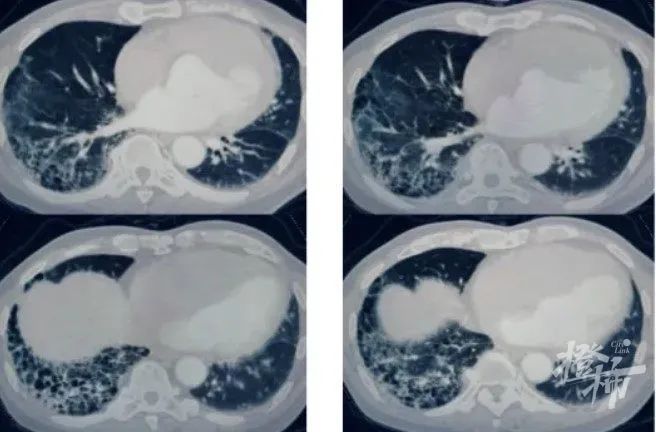

r沈凌医生立即为病人安排了肺部CT检查,在查看影像资料时,他惊讶地发现,王大伯肺部已经出现明显的肺纤维化特征,更为严重的是,局部已经形成了蜂窝状的病变形态。